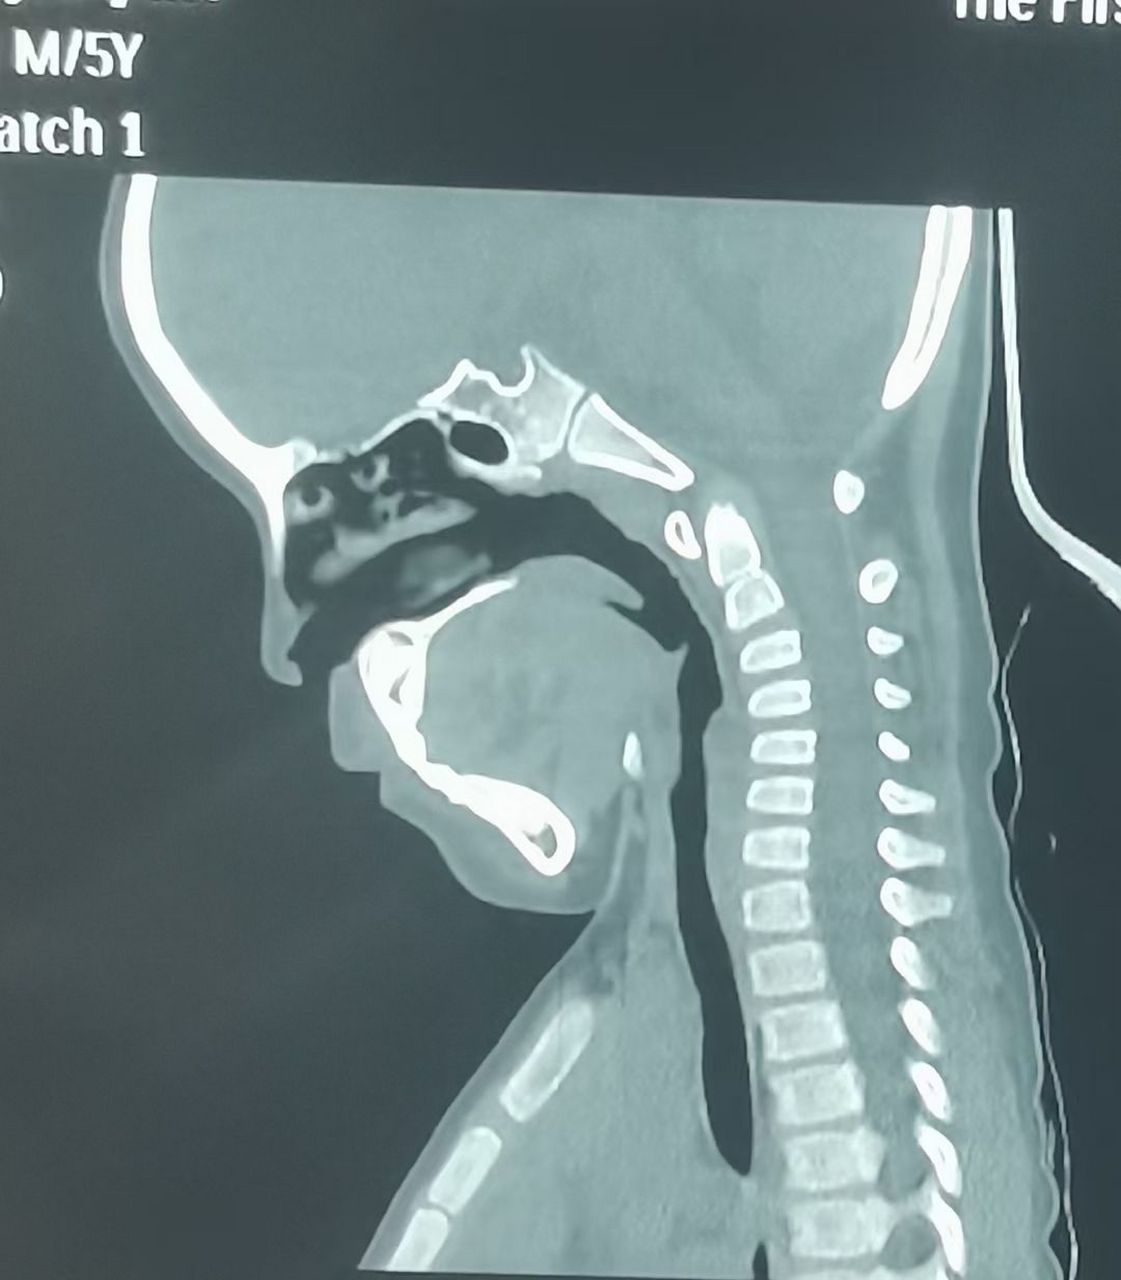

很难想象这是一个5岁的孩子颈椎,电子产品的毒害,颈椎反弓严重!